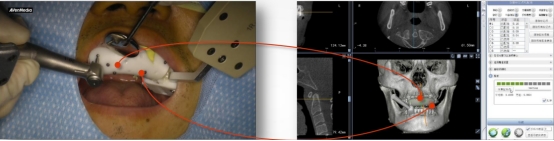

目前,公司拥有全球领先的口腔种植动态导航系统,口腔修复种植科主任董强、副主任田艾带领下的医护团队,大量开展全数字化口腔种植修复治疗。通过使用口腔种植动态导航系统,使种植技术更加“精准、安全、微创、高效”。

高精准度:采用国际领先的红外光学定位技术,准确为医生指引方向,准度可达到0.3mm,种植体植入方向、位置、角度、深度一目了然,确保了种植手术的可预期性,显著提高种植精度。

实时引导:全程监控手术工具与解剖结构的位置关系,轻松把控种植位点、角度和深度,实时引导术者按计划进行种植。

数字化动态导航系统犹如口腔中的GPS导航”,简单来说就是通过虚拟数字化软件设计,提前设计好修复体三维位置,结合精准的红外光学定位技术,在种植手术过程中,实现全程实时的导航。使使种植医生实时监控和调整手术的进程。